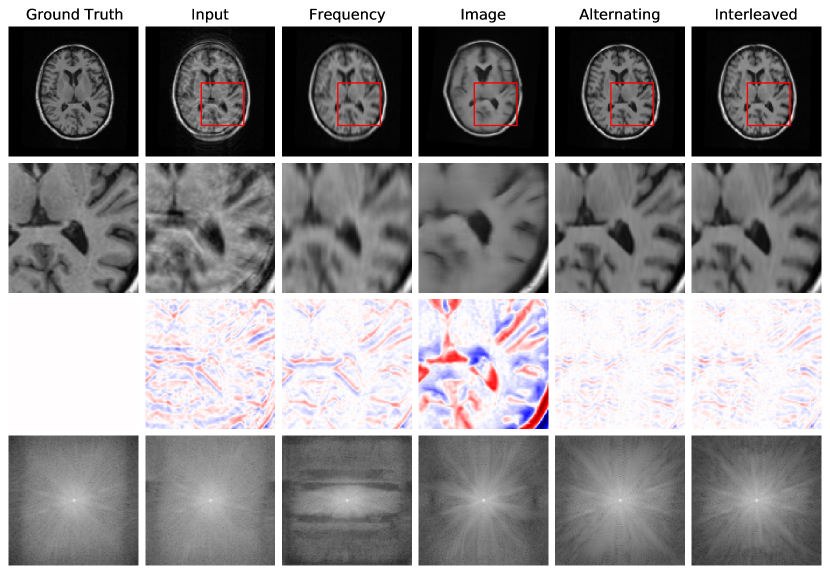

Fig. 4 reports reconstruction quality statistics for all four types of simulations described in Section 4.1.1: motion, noise, undersampling, and motion combined with undersampling. The Interleaved and Alternating architectures outperform the baseline architectures for nearly every task and subject. Across all tasks and nearly all subjects, the Interleaved and Alternating architectures are quite similar in numerical performance. Sample image reconstructions for the motion, motion with undersampling and denoising tasks are shown in Figs. 5-7. Qualitatively, for each task, the Frequency network provides a blurry version of the ground truth image. The Image network provides a reconstruction which effectively removes ‘background’ effects but has limited success in correcting these artifacts within the image. In contrast, the Interleaved and Alternating networks provide sharper, high-quality reconstructions across all tasks. Further, the frequency space reconstructions provided by those networks appear the most faithful to the ground truth frequency data.